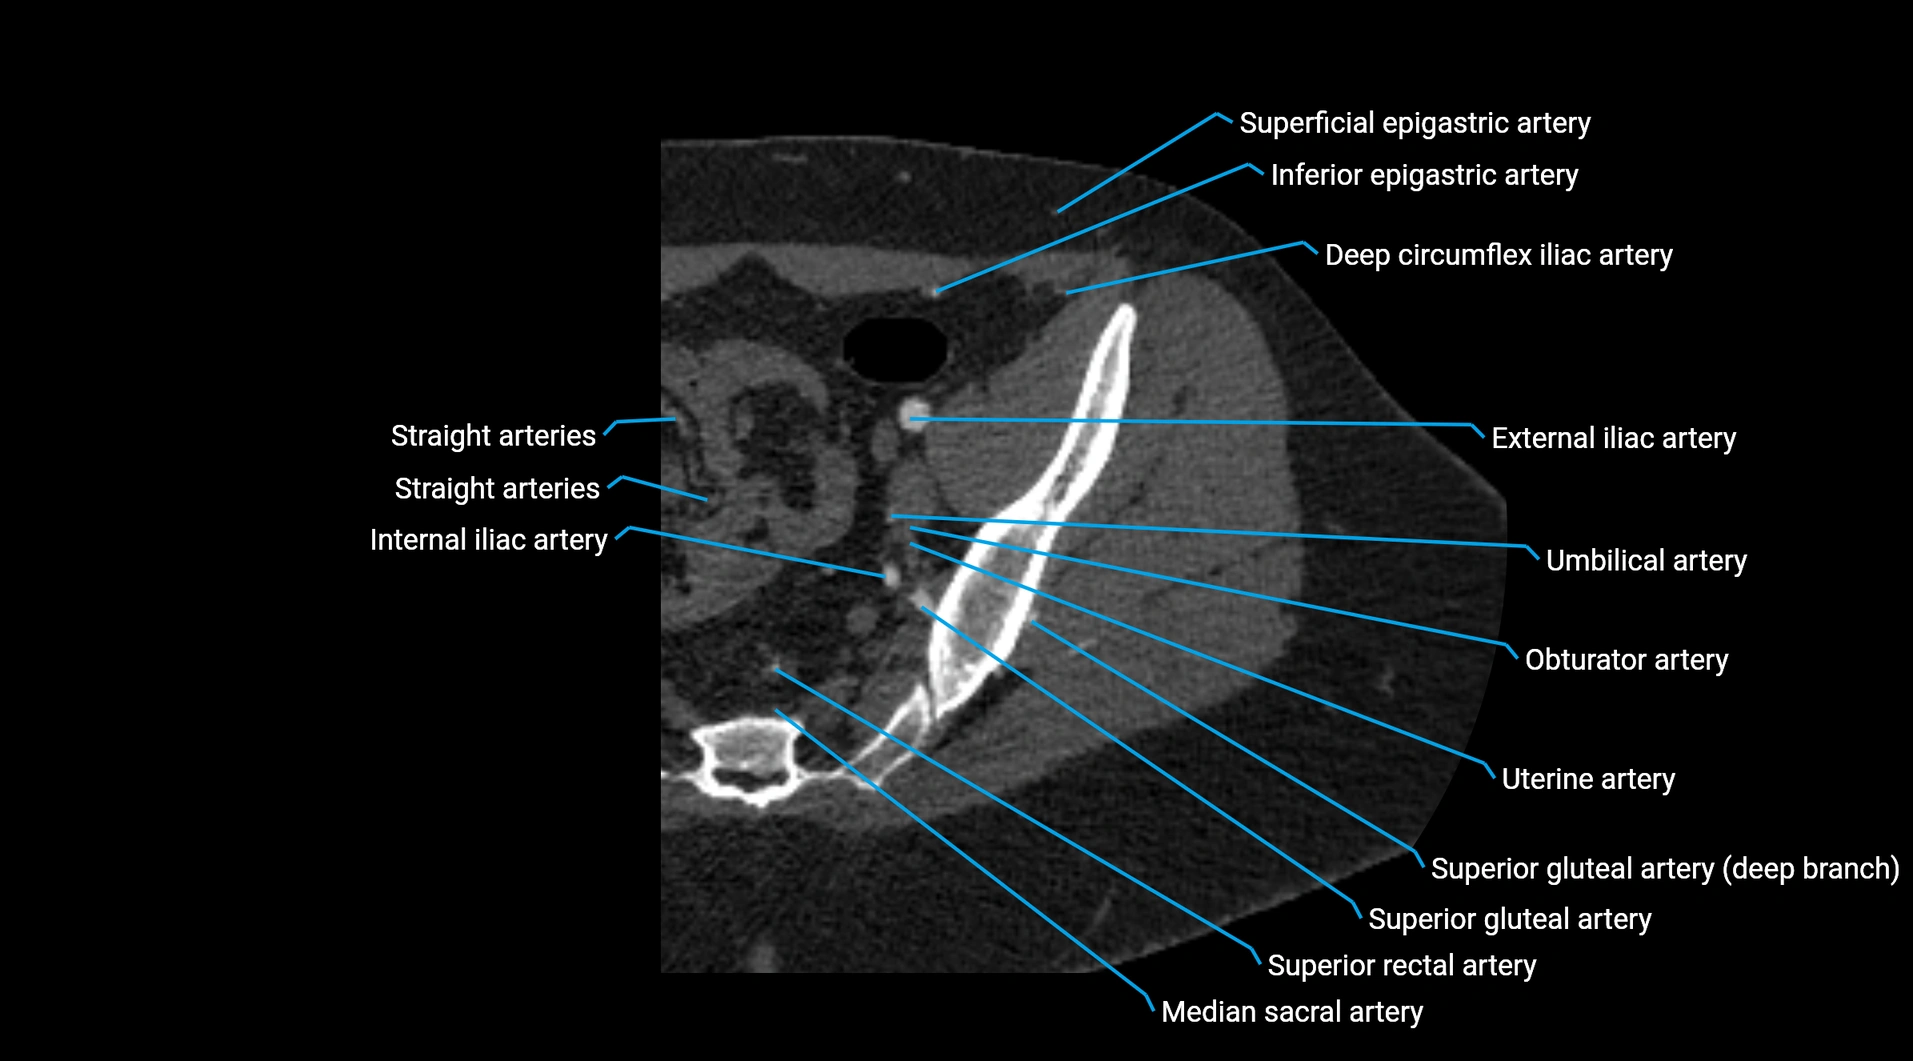

Contrast-enhanced CT (CTA):

• Gold standard for abdominal aortic imaging

• Provides excellent detail of lumen, wall, aneurysm, thrombus, and branch vessels

• Multiplanar and 3D reconstructions help in aneurysm measurement, stent graft planning, and dissection evaluation

• Unpaired visceral branches: celiac trunk, superior mesenteric artery (SMA), inferior mesenteric artery (IMA)

• Paired visceral branches: middle suprarenal arteries, renal arteries, gonadal arteries (testicular or ovarian)

• Parietal branches: inferior phrenic arteries, lumbar arteries, median sacral artery

• Terminal branches: right and left common iliac arteries